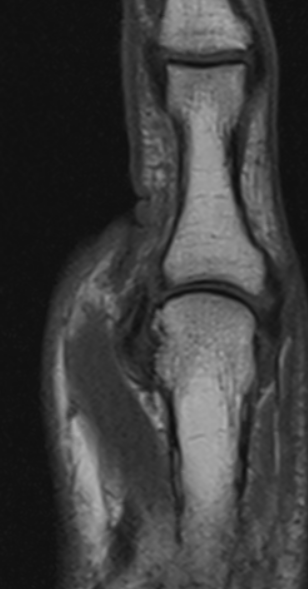

Stener Lesion - Ulnar Collateral ligament tear